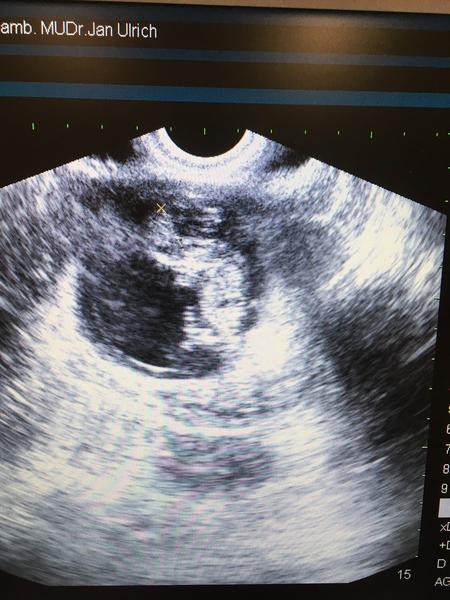

@tobiaskababo ak ti poranili krcok, mozes slabsie zaspinit, ak porania sliznicu v maternici, je to neziaduce pre uhniezdenie. Vela krvacania je nestandardne. Ja som mala posledne tri vklady tiez problem s vkladom. Preto som radsej isla na HSk, maternica ok, len je zaklonena, ale to by sikovny lekar mal zvladnut. Staci pouzit taku pomocnu vôdzku, taku rurku, ta sa strci cez krcok a branku ako prva a potom az kateter do tej rurky. Ide to tak v pohodicke. Pri dalsich vkladoch na to treba upozornit, ze bol problem. A vzdy robit vklady s UTZ.